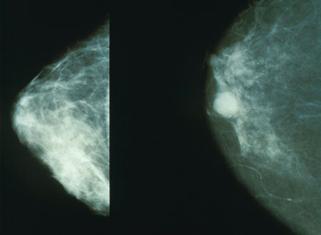

Fig. nr. 4 Mamografii (normal- stg, cancer- dr)

Elem care sugereaza un cc : opacitate cu contur difuz, spiculi, microcalcificari, edem peritumoral (halou transparent), ingrosarea lizereului cutanat